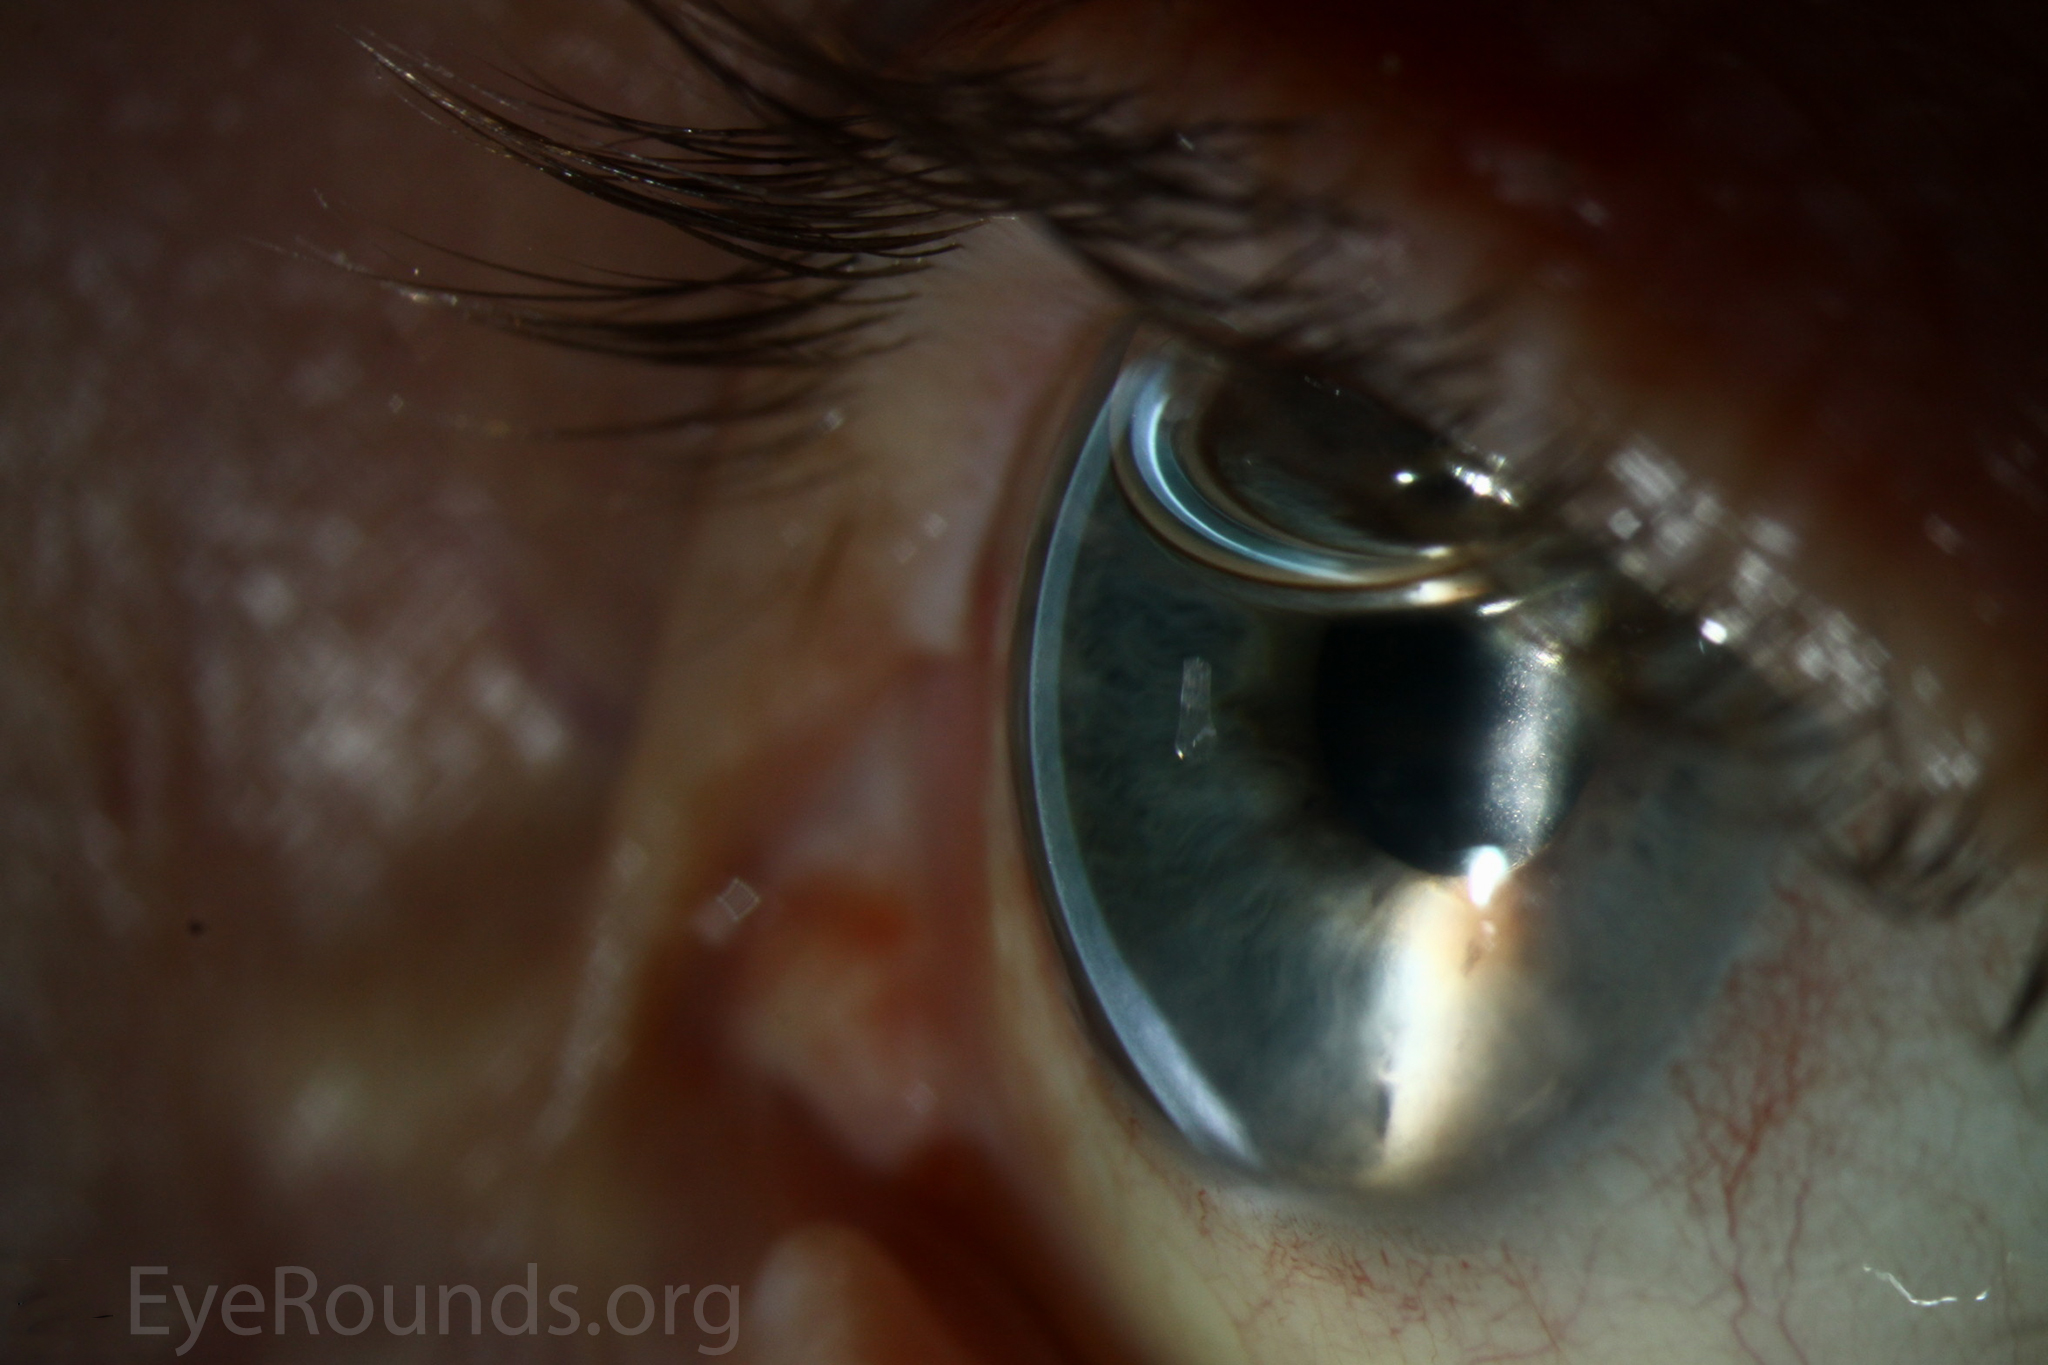

Keratoprosthesis, the transplantation of an artificial cornea, was first performed in Italy by Benedetto Strampelli the 1960s (1). Patients requiring repeat corneal transplantation highlighted the need for an alternative to corneal allograft treatment, as graft survival rates drop with each additional procedure. Historical options have included the osteo-odonto-keratoprosthesis (OOKP) and AlphaCor artificial cornea. These have since been largely replaced by the Boston Type I Keratoprosthesis (KPro), which became approved for use by the U.S. Food and Drug Administration in 1992 (1, 13). The device consists of a clear plastic optic and a prosthetic plate that are sandwiched around a donor allograft or the patient's own corneal tissue. The device is then sutured onto the recipient eye to replace a failed graft or the native cornea. Keratoprosthesis surgery is a procedure of last-resort, reserved for patients who are not candidates for other types of keratoplasty.

Keratoprosthesis implantation is a procedure that involves full-thickness removal of the cornea and replacement by an artificial cornea. The Boston Type I Keratoprosthesis is currently the most commonly used keratoprosthesis device in the US. It consists of a clear plastic polymethylmethacrylate (PMMA) optic and back plate sandwiched around a corneal graft and secured with a titanium locking ring (Figure 15). After the device is assembled, a partial-thickness trephination is performed on the host cornea. Full-thickness resection of the patient's cornea is then completed using curved corneal scissors. The keratoprosthesis is then secured to host tissue using interrupted or running sutures. Generally, patients who have a history of multiple failed PKs are candidates for a keratoprosthesis transplant. Other indications include severe keratitis or ocular surface disease resulting from limbal stem cell failure, such as Stevens-Johnson syndrome (Figure 16), ocular cicatricial pemphigoid, aniridia (Figure 17) and chemical injury (1, 13). The Boston Type II Keratoprosthesis is a similar device with a longer optic designed to extend through an opening made in the upper eyelid (Figure 19). It is indicated for the most severe cicatrizing ocular surface diseases.

KPro placement offers relatively fast visual rehabilitation. The devices are amenable for use in many situations in which other types of keratoplasty are not an option.

There is significant long-term risk of complications for those with a keratoprosthesis. Because the KPro is a foreign body, there is risk of infection or extrusion of the device. Post-operative glaucoma is common and intraocular pressure is difficult to evaluate as the hard optic makes traditional tonometry impossible. For this reason, glaucoma tube shunts are typically placed at the time of the corneal transplant at the University of Iowa. The Diaton is currently the preferred way to measure intraocular pressure in these patients in our institution. Patients can form retroprosthetic membranes requiring treatment with a Nd:YAG laser or surgical membranectomy (21).